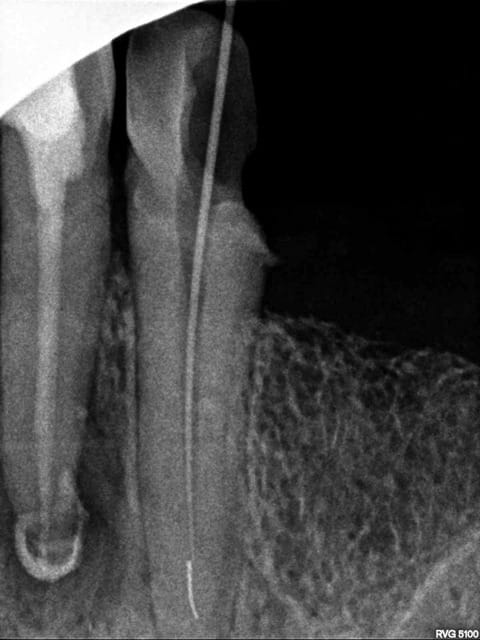

Voila mes deux perles, je me doute bien que l'infection sur la 46 a peu de chance de disparaitre, mais on remarquera sur la 13 la belle continuité de l'instrument sur le gutta qui cache bien son jeu! :-))

Sur ta 46, le pronostic est assez mauvais. Il y a plus d'espoir avec la prémolaire.

pour moi, toutes les dents qui sont représentées sur tes radios sont à extraire maintenant en raison d'une lésion préexistante. Tu as trop de portion de canal non instrumenté pur que tabalanceoit en faveur de la recnstruction osseuse. La molaire était foutue avant l'endo selon moi. ta canine, tu peux eventuellement tenter une resection apicale, mais bon...